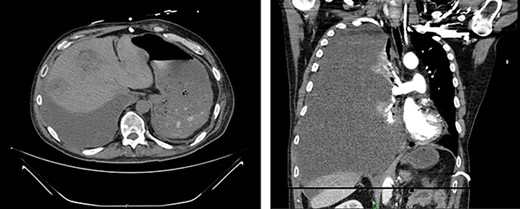

CT demonstrates growth of effusion into the entirety of the right hemithorax with mass effect shifting all thoracic contents to the left (left); later cytology ruled out malignant effusion; substantial increase in liver metastatic lesions can also be seen when compared to previous images from 2 months prior.

Fourteen weeks post-resection, the patient presented to the ED for symptoms of pneumonia and again tested positive for COVID-19. Chest X-ray showed evidence of small, right-sided pleural effusion. He was discharged for home quarantine. Ten days later, he returned to the ED with worsening shortness of breath and chest pain. CT showed a nonmalignant effusion filling the entire right hemithorax as well as significant enlargement of liver lesions (Fig. 5). He was discharged a week later following symptomatic improvement but experienced an exacerbation of respiratory symptoms soon after and was readmitted.